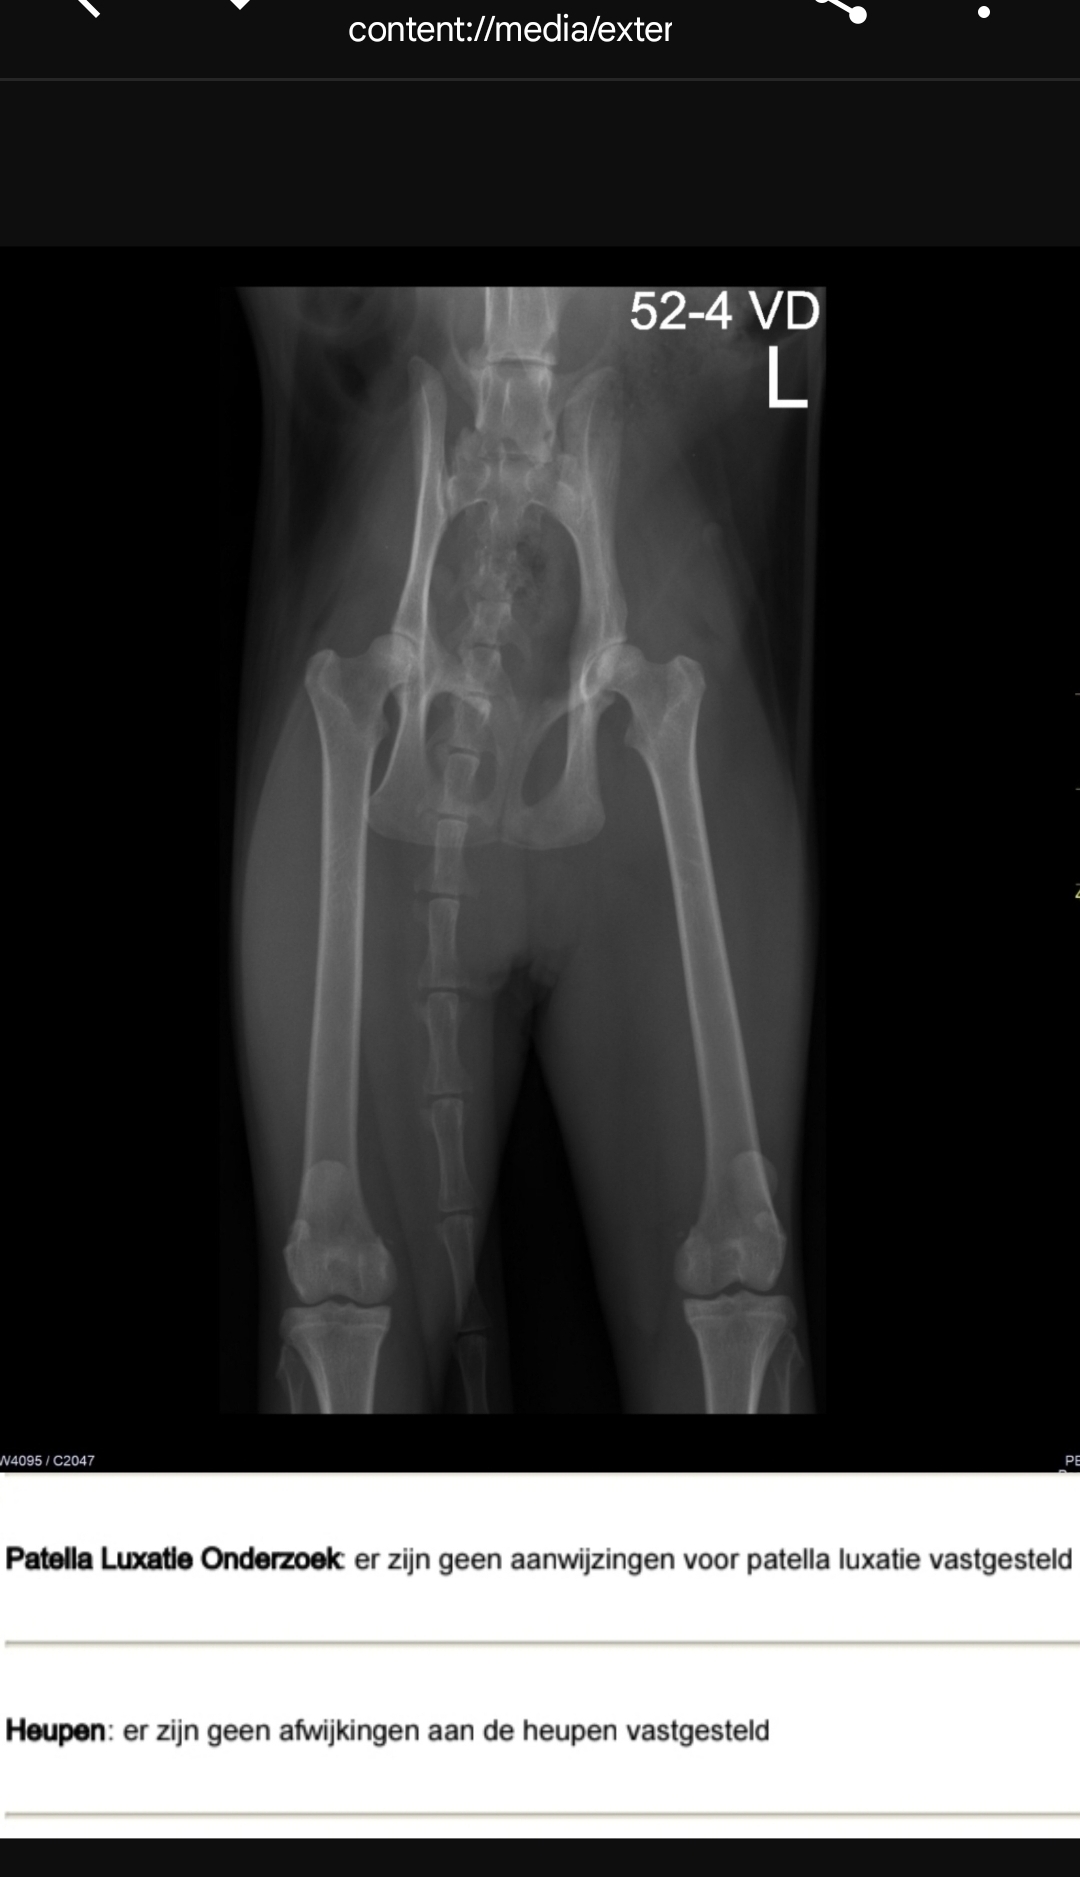

Heupen

Afbeelding – 400,9 KB

41 downloads

Download